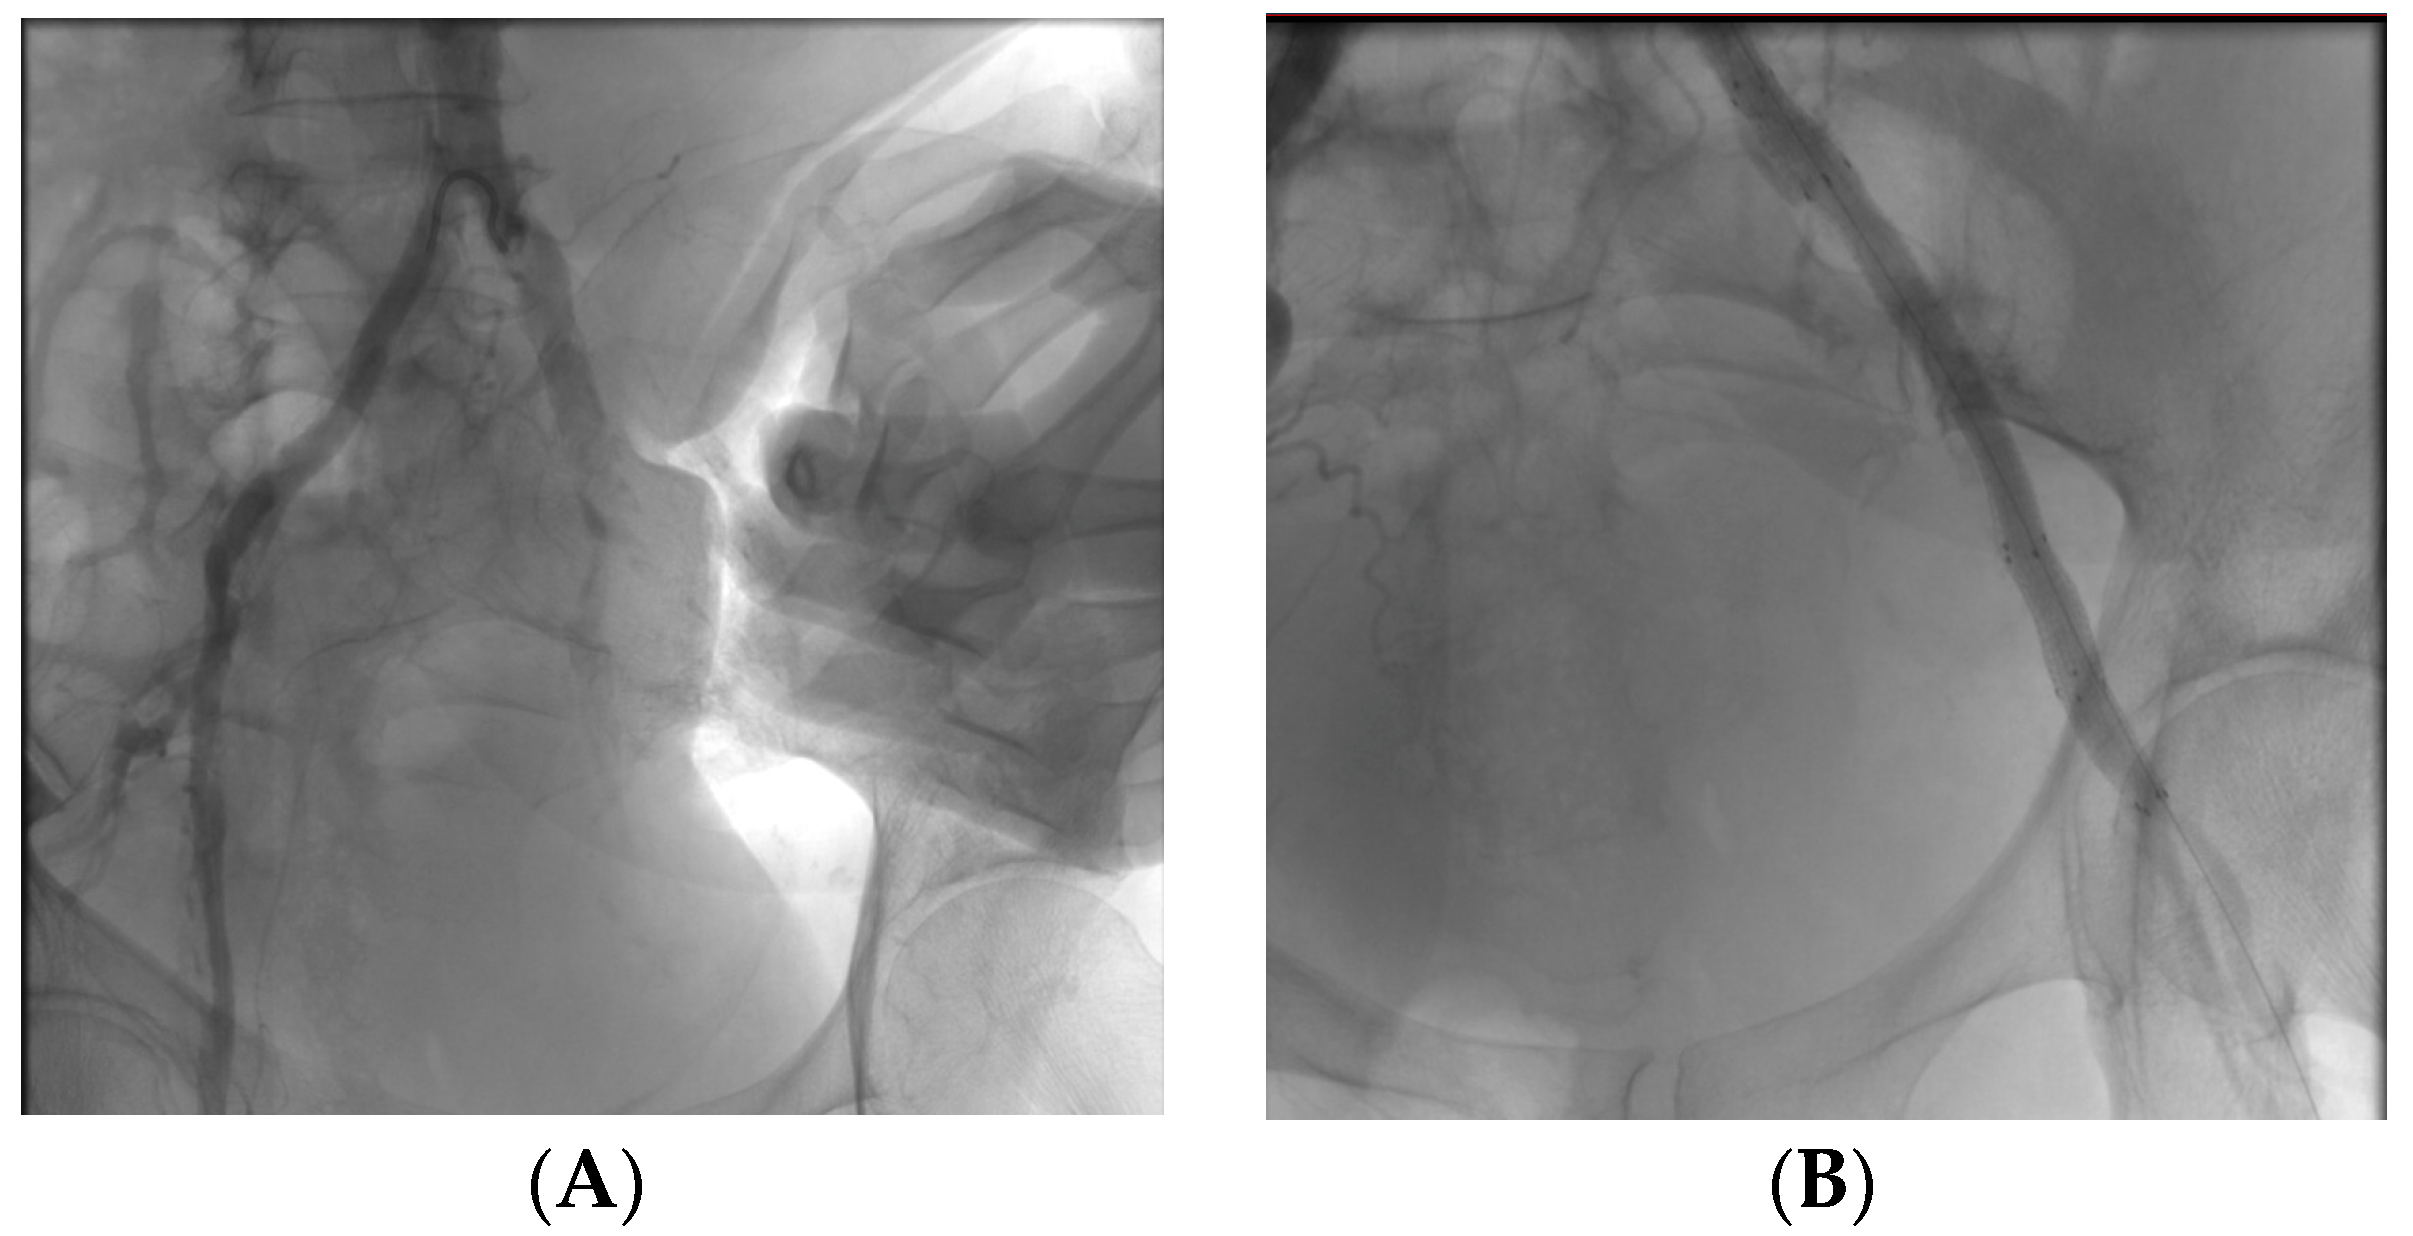

An 87-year-old patient with paroxysmal atrial fibrillation comes to the emergency department for coldness and pallor in the right lower extremity. He undergoes urgent ECD (echocolorDoppler) and low molecular weight heparin. The ECD reveals a dilation of the right popliteal artery, so a CT scan with contrast medium is requested, which shows the presence of a popliteal aneurysm with partial parietal thrombosis. The patient was a candidate for endovascular surgery via antegrade ultrasound access to the ipsilateral common femoral artery; intraoperative angiography was performed from the diagnostic catheter, which showed the presence of the popliteal aneurysm and the landing zones for proper stent release. After removal of the angiographic catheter, a VIABAHN 9.0 × 150 mm e-PTFE coated stent was released into the right popliteal artery with subsequent reshaping using a MUSTANG angioplasty balloon. Intra-operative and post-operative follow-up (ECD) revealed complete patency of the stent and absence of endoleak.

Figure A1. Angiogram of pre- (A), during (C) and post- (B) endovascular treatment.